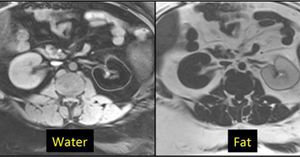

Although generally better than CHESS/Fat-Sat sequences, modern Dixon methods still have their limitations, particularly in highly inhomogeneous areas like the neck and around metal hardware. A curious artifact occasionally occurs wherein the mathematical computations will converge to the wrong substance, producing a fat-only image when a water-only image is desired. An interesting example of this so-called "fat-water swap" is shown below. Fig. Failure of local convergence in IDEAL sequence with fat-water swap. The normal left kidney has been mistakenly identified as composed of fat rather than water.